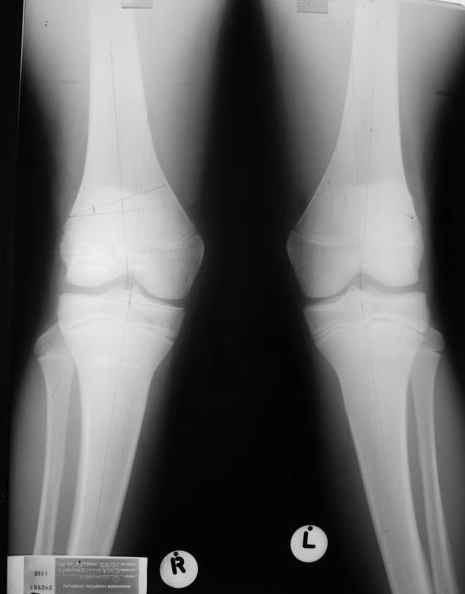

Как вариант решения прогрессирующей вальгусной деформации коленного сустава я бы предложил косую остеотомию дистального отдела бедра с фиксацией пластиной и компрессирующим винтом.

Взгляните на снимки , может быть это вам поможет.

Уважаемый Евгений ! Спасибо за ответ, но мне представляется, что в нашем случае основной проблемой является не столько прогрессирующий вальгус конечности, сколько несросшийся перелом мыщелка бедра и дефект мыщелка большеберцой кости - вероятно первичная репозиция выполнялась без пластики.

Мне представляется, что прогрессирующий вальгус и обусловлен несросшимся переломом мыщелка бедра (томограммы -зона межфрагментарного склерозирования), а циклические нагрузки на сустав во время ходьбы усугубляют ситуацию. Как вы думаете, в этой ситуации насколько вероятен риск развития аваскулярного некроза мыщелка бедра?

Относительно "рубцовой подушки" я имел в виду остатки мениска ( частично вколоченного в дефект мыщелка и фрагменты хряща), все таки на рентгенограммах суставная щель в этом отделе чем то заполнена. Что касается некроза мыщелка бедра, то мне кажется он уже наступил - томограмма ноябрь5.

С учетом всего сказанного - наличия прогессирующего вальгуса конечности, довольно приличного объема движений, имеющегося, вероятно, некроза мыщелка бедра, наиболее рациональным представляется удалить пластину с б\б кости, произвести остеотомию б\б кости с коррекцией вальгуса, разгрузив тем самым наружный отдел сустава, и синтезировать фрагменты голени накостным фиксатором. Максимально тано начать восстановление движений в суставе. Скорее всего рано или поздно речь о протезировании всеже возникнет, но мы хотя бы будем иметь приличную ось конечности.

С *вколоченным* мениском встречаться не приходилось, нередко при импрессионных переломах наблюдал центральную дислокацию мениска по типу bucket handle, что в этой ситуации может объяснить сгибание сустава до 90 и разгибание 160 градусов, отчасти невозможность полностью разогнуть ногу при Рг графии сустава затрудняет интерпретацию прямой проекции сустава.

Сканирование с Тс99 поможет верифицировать наличие некроза мыщелка бедра, если использовались титановые винты, то магнитно-резонансное исследование будет более информативным. При подтверждении некроза, бедренная или всокая тибиальная остеотомии, очевидно, будут малоуспешны, поэтому альтернатив артропластике похоже не останется. Наблюдений реваскуляризации мыщелка бедра после туннелизации у меня нет, надо покопаться в литературе.